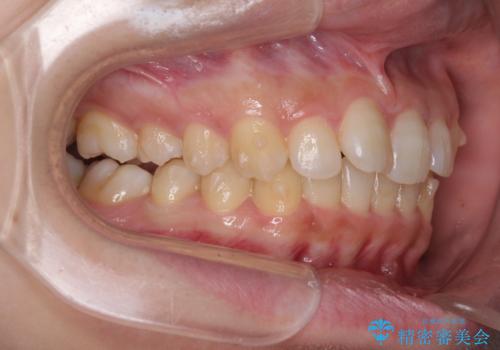

- 前歯のデコボコと奥歯の不正咬合を気にして来院された患者様です。

左右の大臼歯が全て鋏状咬合(シザーズバイト)になっており、治療が難航することが予想されましたが、インビザラインにより治療を行うこととしました。